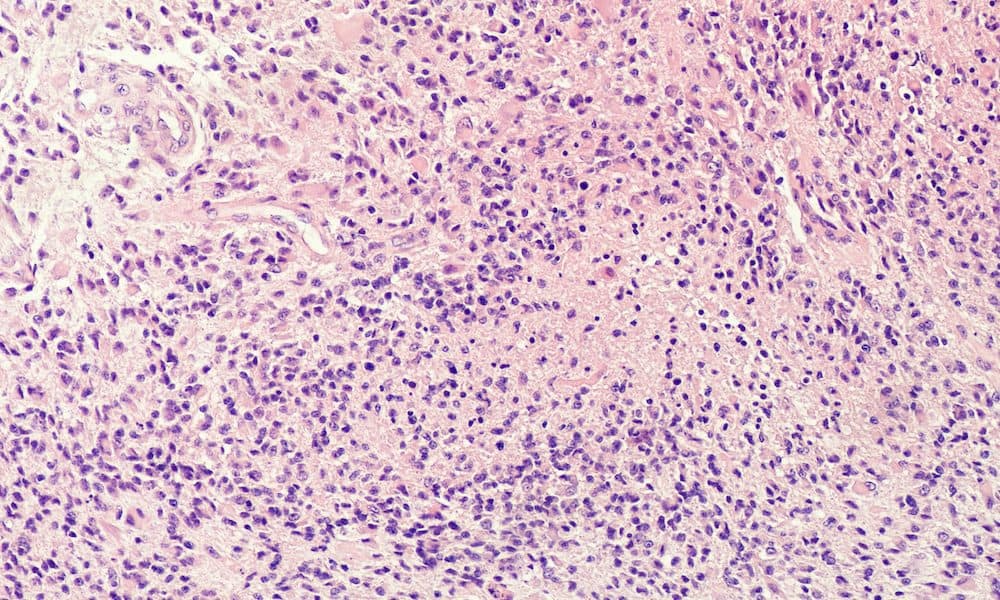

While breakthroughs in cancer treatment over the past 40 years have been truly life-changing, with recovery prospects and life expectancy in many common cancers revolutionised, that sadly is not true with regard to glioblastoma (GBM).

A particularly aggressive form of brain tumour, the outlook for GBM patients continues to be bleak, with the average survival time being just 12 to 18 months despite an intensive treatment regime comprising surgery, chemotherapy and radiotherapy.

Only a quarter of people diagnosed with GBM survive for longer than this, with just five per cent still alive five years later.